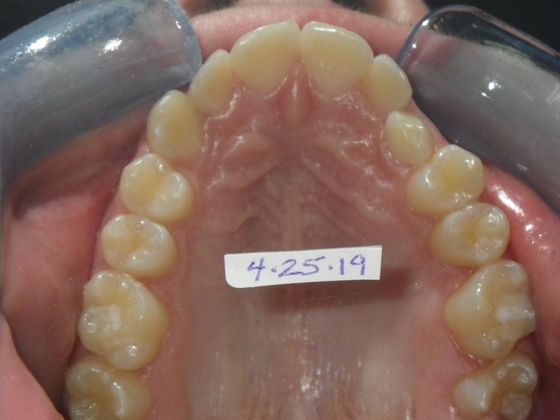

This patient had an upper right permanent cuspid that was impacted and would need uncovering by oral surgeon who would place bracket with chain to help enable us to tease the permanent cuspid into its proper position. She also had a permanent 2nd Molar that was impacted due to improper development of 3rd molars and the oral surgeon could remove them at the same time as uncovering of the permanent cuspid. After uncovering and removal of lower 3rd molars, we would begin comprehensive straight wire orthodontic treatment.